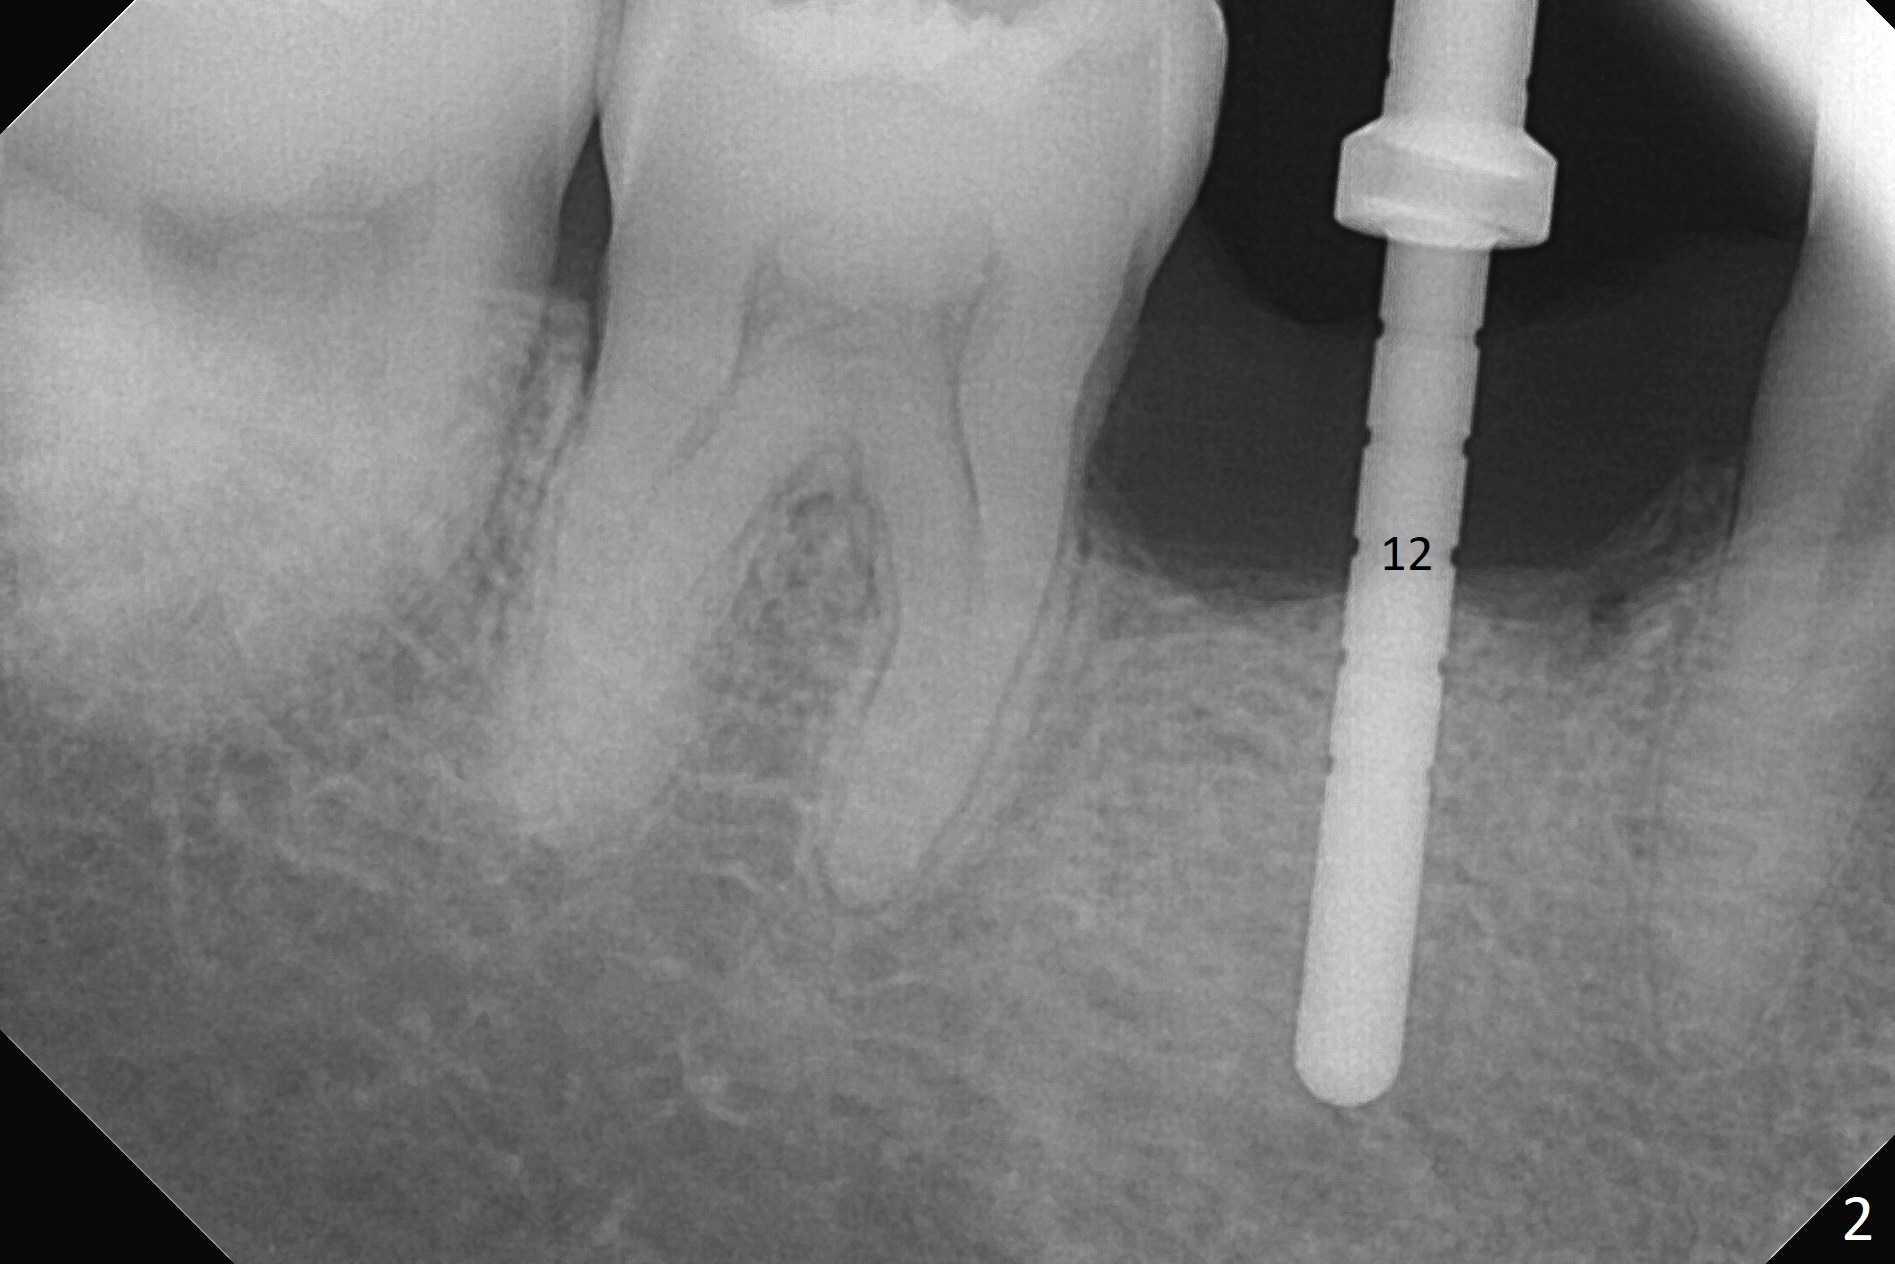

The retained deciduous tooth (lower right 2nd molar, Fig.1 T) has buccal apical infection and recession. After extraction, the initial depth of osteotomy is 11 mm over the flat socket bottom (Fig.2) without visible Mental Loop. Following 3.8 mm Magic Drill for 11 mm, a 4x11 mm dummy implant is placed partially due to hard bone; it appears that the apical osteotomy (Fig.3 yellow outline) overlaps the Mental Loop (red dashed line). For safety, a 4x9 mm IBS implant is placed with insertion torque 40 Ncm; a 5x5.7(4) mm abutment is immediately placed for an immediate provisional to cover the large socket and keep Vera graft in place (Fig.4 *). There is no postop paresthesia, probably due to the fact that the osteotomy is lingual to the Mental Loop. The provisional remains in place 7 days postop; its margin (Fig.5 arrow) covers the socket. The margin of the provisional is trimmed 1 month postop. Impression is taken nearly 3 months postop (Fig.6). The buccal plate looks atrophic 3 months postop (Fig.7 (immediately before cementation)), although there is no sign of periimplantitis. In the future, insert the immediate provisional inside of the buccal gingiva to make the buccal gingiva look bulky instead of buccal to it (Fig.5). The second drawback of placing an implant at the deciduous tooth area is that the crown is wide mesiodistally if orthodontic treatment is not rendered. Although there is lower anterior crowding, the patient declines orthodontic treatment. The bone density around the implant increases 7 months post cementation (Fig.8 *). The higher density bone seems to extend coronally 1 year 7 months post cementation (Fig.9). The dense bone apparently extends toward the abutment as well 3 years 5 months post cementation (Fig.10 curved arrows).